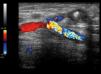

Our first patient was a 78-year old female on haemodialysis since 2009 with a left humerocephalic AVF. The patient developed oedema in the arm with the AVF, which produced progressively worsening pain and functional impairment. The patient was diagnosed with occlusion of the subclavian vein, and several attempts at PTA resulted in early recurrence. We decided to place a right central venous catheter and to close the AVF due to poor functioning. The AVF was annulled through ultrasound-guided injection of thrombin (Figure 1) into the cephalic vein, producing thrombosis. Ten days later, the oedema had disappeared and the artery was again patent with no symptoms.

Figure 1. Humerocephalic anastomosis following the injection of thrombin